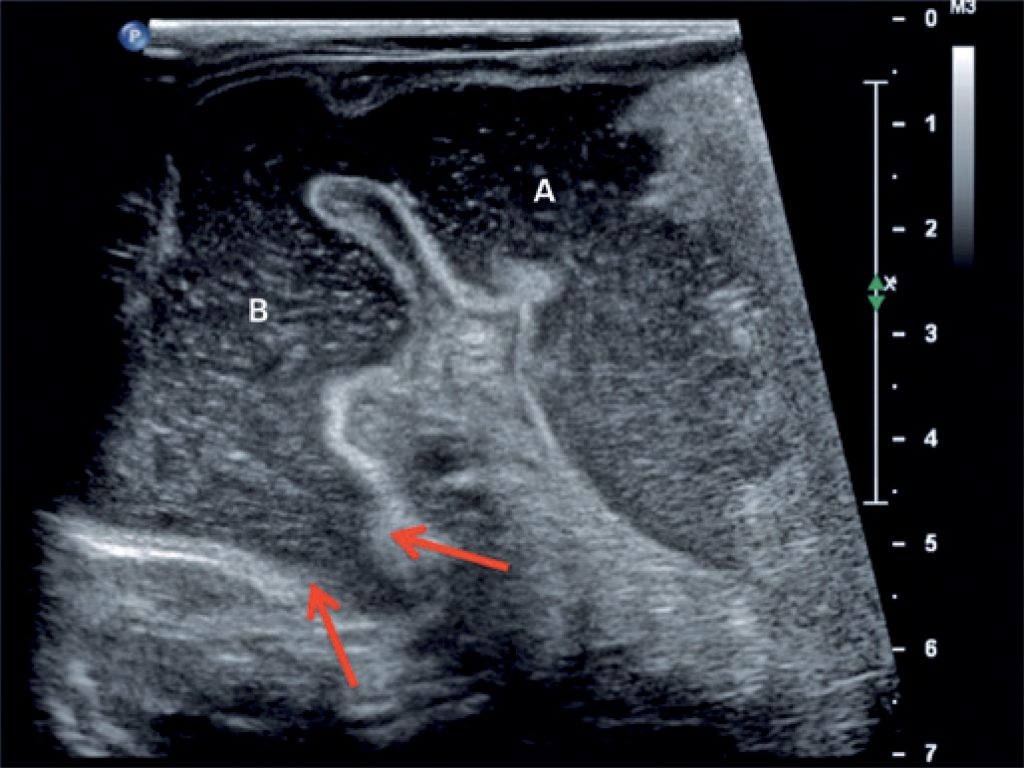

Vomiting episodes in newborns are extremely common and often attributed to gastroesophageal reflux. The symptoms of vomiting, however, may be caused by other complications. In this report, we present two cases of a 1-month-old male and a 2-month-old female, both presenting vomiting episodes that led to malnutrition. Some pediatricians often attribute the diagnosis of gastroesophageal reflux to newborns that are vomiting; however, there is a portion of the population that has other causes that lead to similar symptoms. The pediatrician should be alert to the clinical signs of weight loss, dehydration and malnutrition to investigate other causes of vomiting.